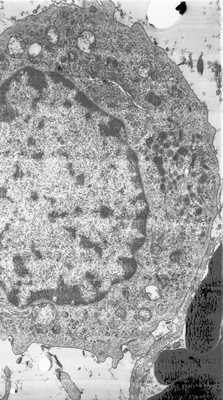

Вместе с тем микобактерии обладают способностью изменять рН цитоплазмы и «арестовывать» эндосомы макрофага [16]. Это означает, что основная масса лизосом будет израсходована на разрушение микобактерий, а новые не образуются. Таким образом, макрофаг практически лишается лизосом и трансформируется в эпителиоидную клетку, которая сохраняет функцию фагоцитоза, но не способна образовывать фагоцитарную вакуоль. В ней почти нет лизосом (рис. 2), Рисунок 2. Эпителиоидная клетка, в цитоплазме которой микобактерии туберкулеза и лишь единичные лизосомы, не образующие фагоцитарных вакуолей. × 15 000. и она становится резервуаром для сохранения микобактерий, которых еще и защищает своей цитомембраной от действия различных провоспалительных интерлейкинов и других цитокинов, обеспечивая нестерильный иммунитет. Это происходит в конце 2-й недели заболевания, когда появляется гиперчувствительность замедленного типа, однако казеозный некроз формируется позже [15].

Принципиально аналогичная ситуация наблюдается и при лепре, особенно при ее туберкулоидном типе, который также характеризуется образованием иммунной гранулемы, содержащей специфические пенистые макрофаги - клетки Вирхова, лимфоциты и эпителиоидные клетки. Различают два основных типа лепрозных гранулем - лепроматозный и туберкулоидный, между которыми несколько промежуточных типов. Можно провести аналогию между первичным аффектом при туберкулезе и лепроматозным типом лепры, с которого обычно начинается заболевание, когда много лепрозных клеток, т.е. макрофагов, при этом в них также скапливаются микобактерии, что расценивается как эндоцитобиоз, и иммунный ответ выражен отчетливо меньше, чем при туберкулоидном типе лепры. Туберкулоидный тип морфологически весьма схож с эпителиоидно-клеточной туберкулезной гранулемой. Эпителиоидные клетки не содержат лизосом, в них много микобактерий, находящихся в дормантном состоянии, но нет фагоцитарных вакуолей (рис. 3). Рисунок 3. Лепрозная гранулема, туберкулоидный тип. Эпителиоидная клетка содержит микобактерии лепры, но в ее цитоплазме нет лизосом. Сами микобактерии расположены в липидных каплях, образованных жирными кислотами (рис. 4), Рисунок 4. Лепрозная гранулема, туберкулоидный тип. В эпителиоидной клетке микобактерии расположены в липидных каплях, образованных жирными кислотами. которые микобактерии, находясь в дормантном состоянии, используют для своей жизнедеятельности [18]. Подобные же липидные капли в эпителиоидных клетках и в клетках Пирогова-Лангханса обнаруживаются и при туберкулезе.